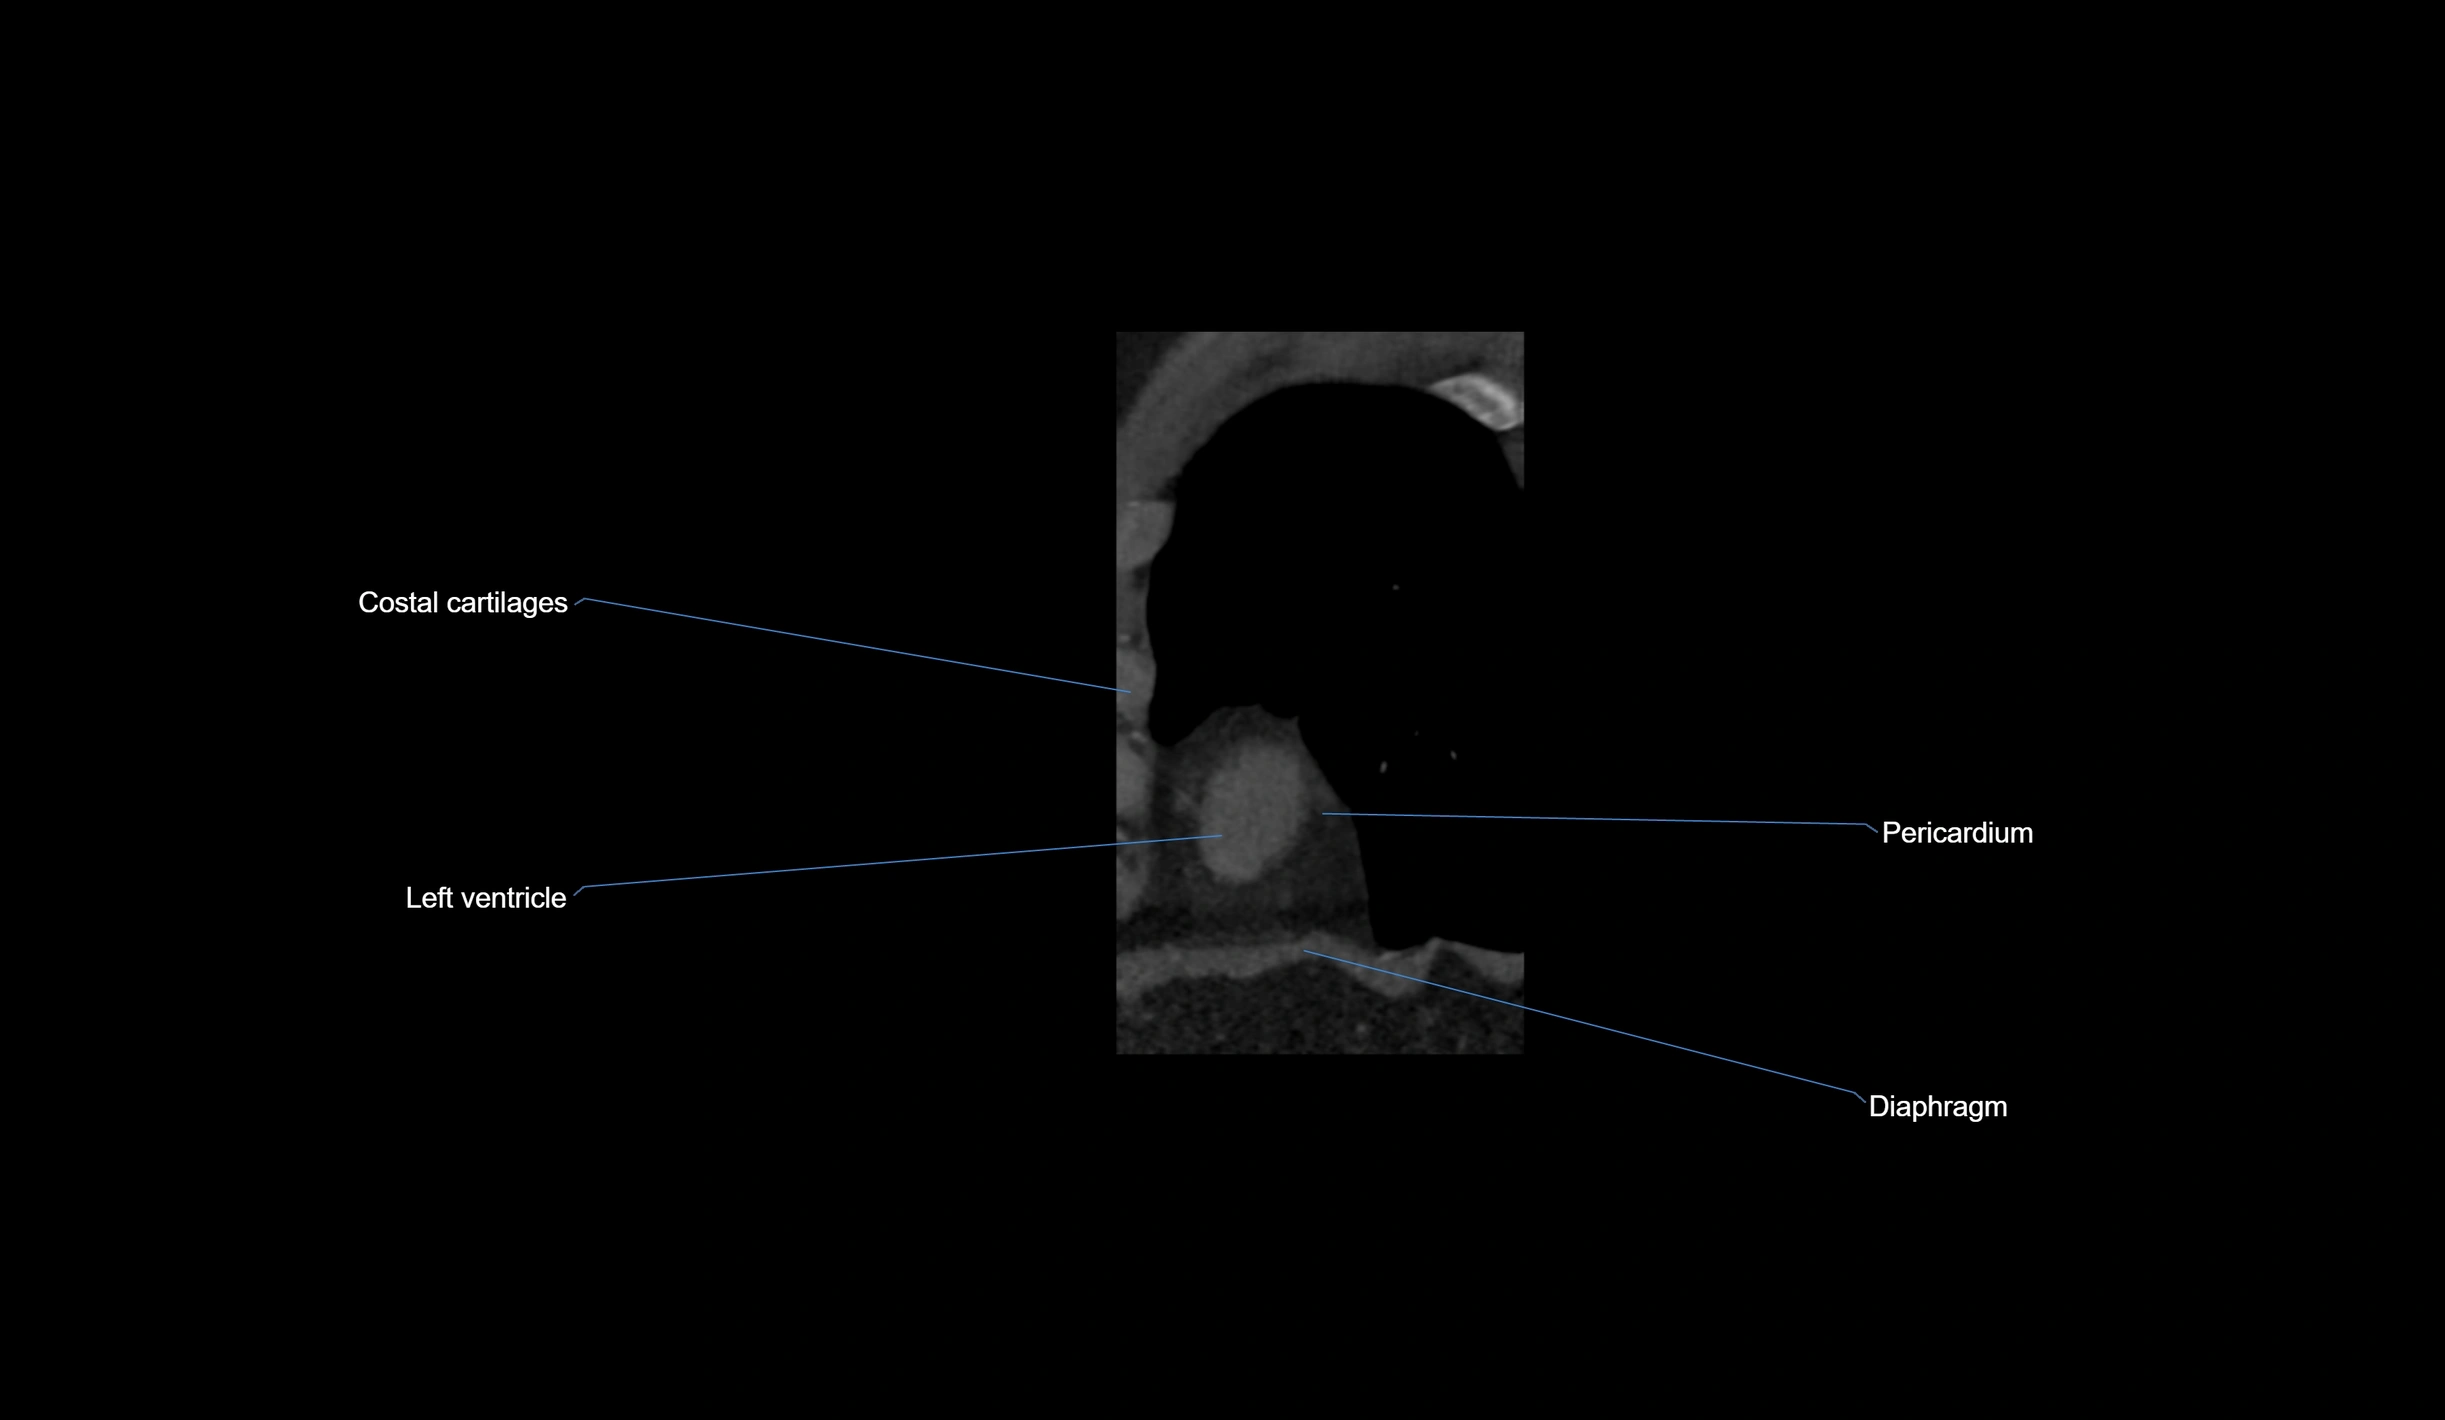

- Costal cartilages

- Diaphragm

- Left ventricle

- Pericardium